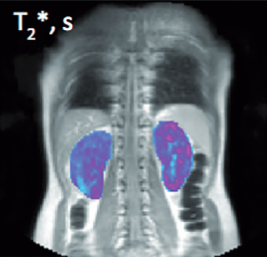

We use dynamic contrast-enhanced MRI (DCE-MRI) to quantify changes in perfusion and endothelial integrity in the presence of inflammation and during treatment. Bioxydyn has defined many of the standard approaches to the technique’s implementation in clinical trials.

DCE-MRI involves the use of standard clinical intravenously-administered gadolinium-based contrast agents. The uptake and washout of the agent is interpreted using physiological modelling methods to provide imaging biomarkers of microvascular function and inflammation.

Bioxydyn uses the Ktrans quantitative biomarker, which can be readily compared between centres. Its relationship to the intensity of inflammation is based on sound and widely accepted science, is extremely sensitive to drug effects, and only requires small patient numbers. The images show change in Ktrans in the joints of the hands and wrist in an individual with rheumatoid arthritis during therapeutic intervention.